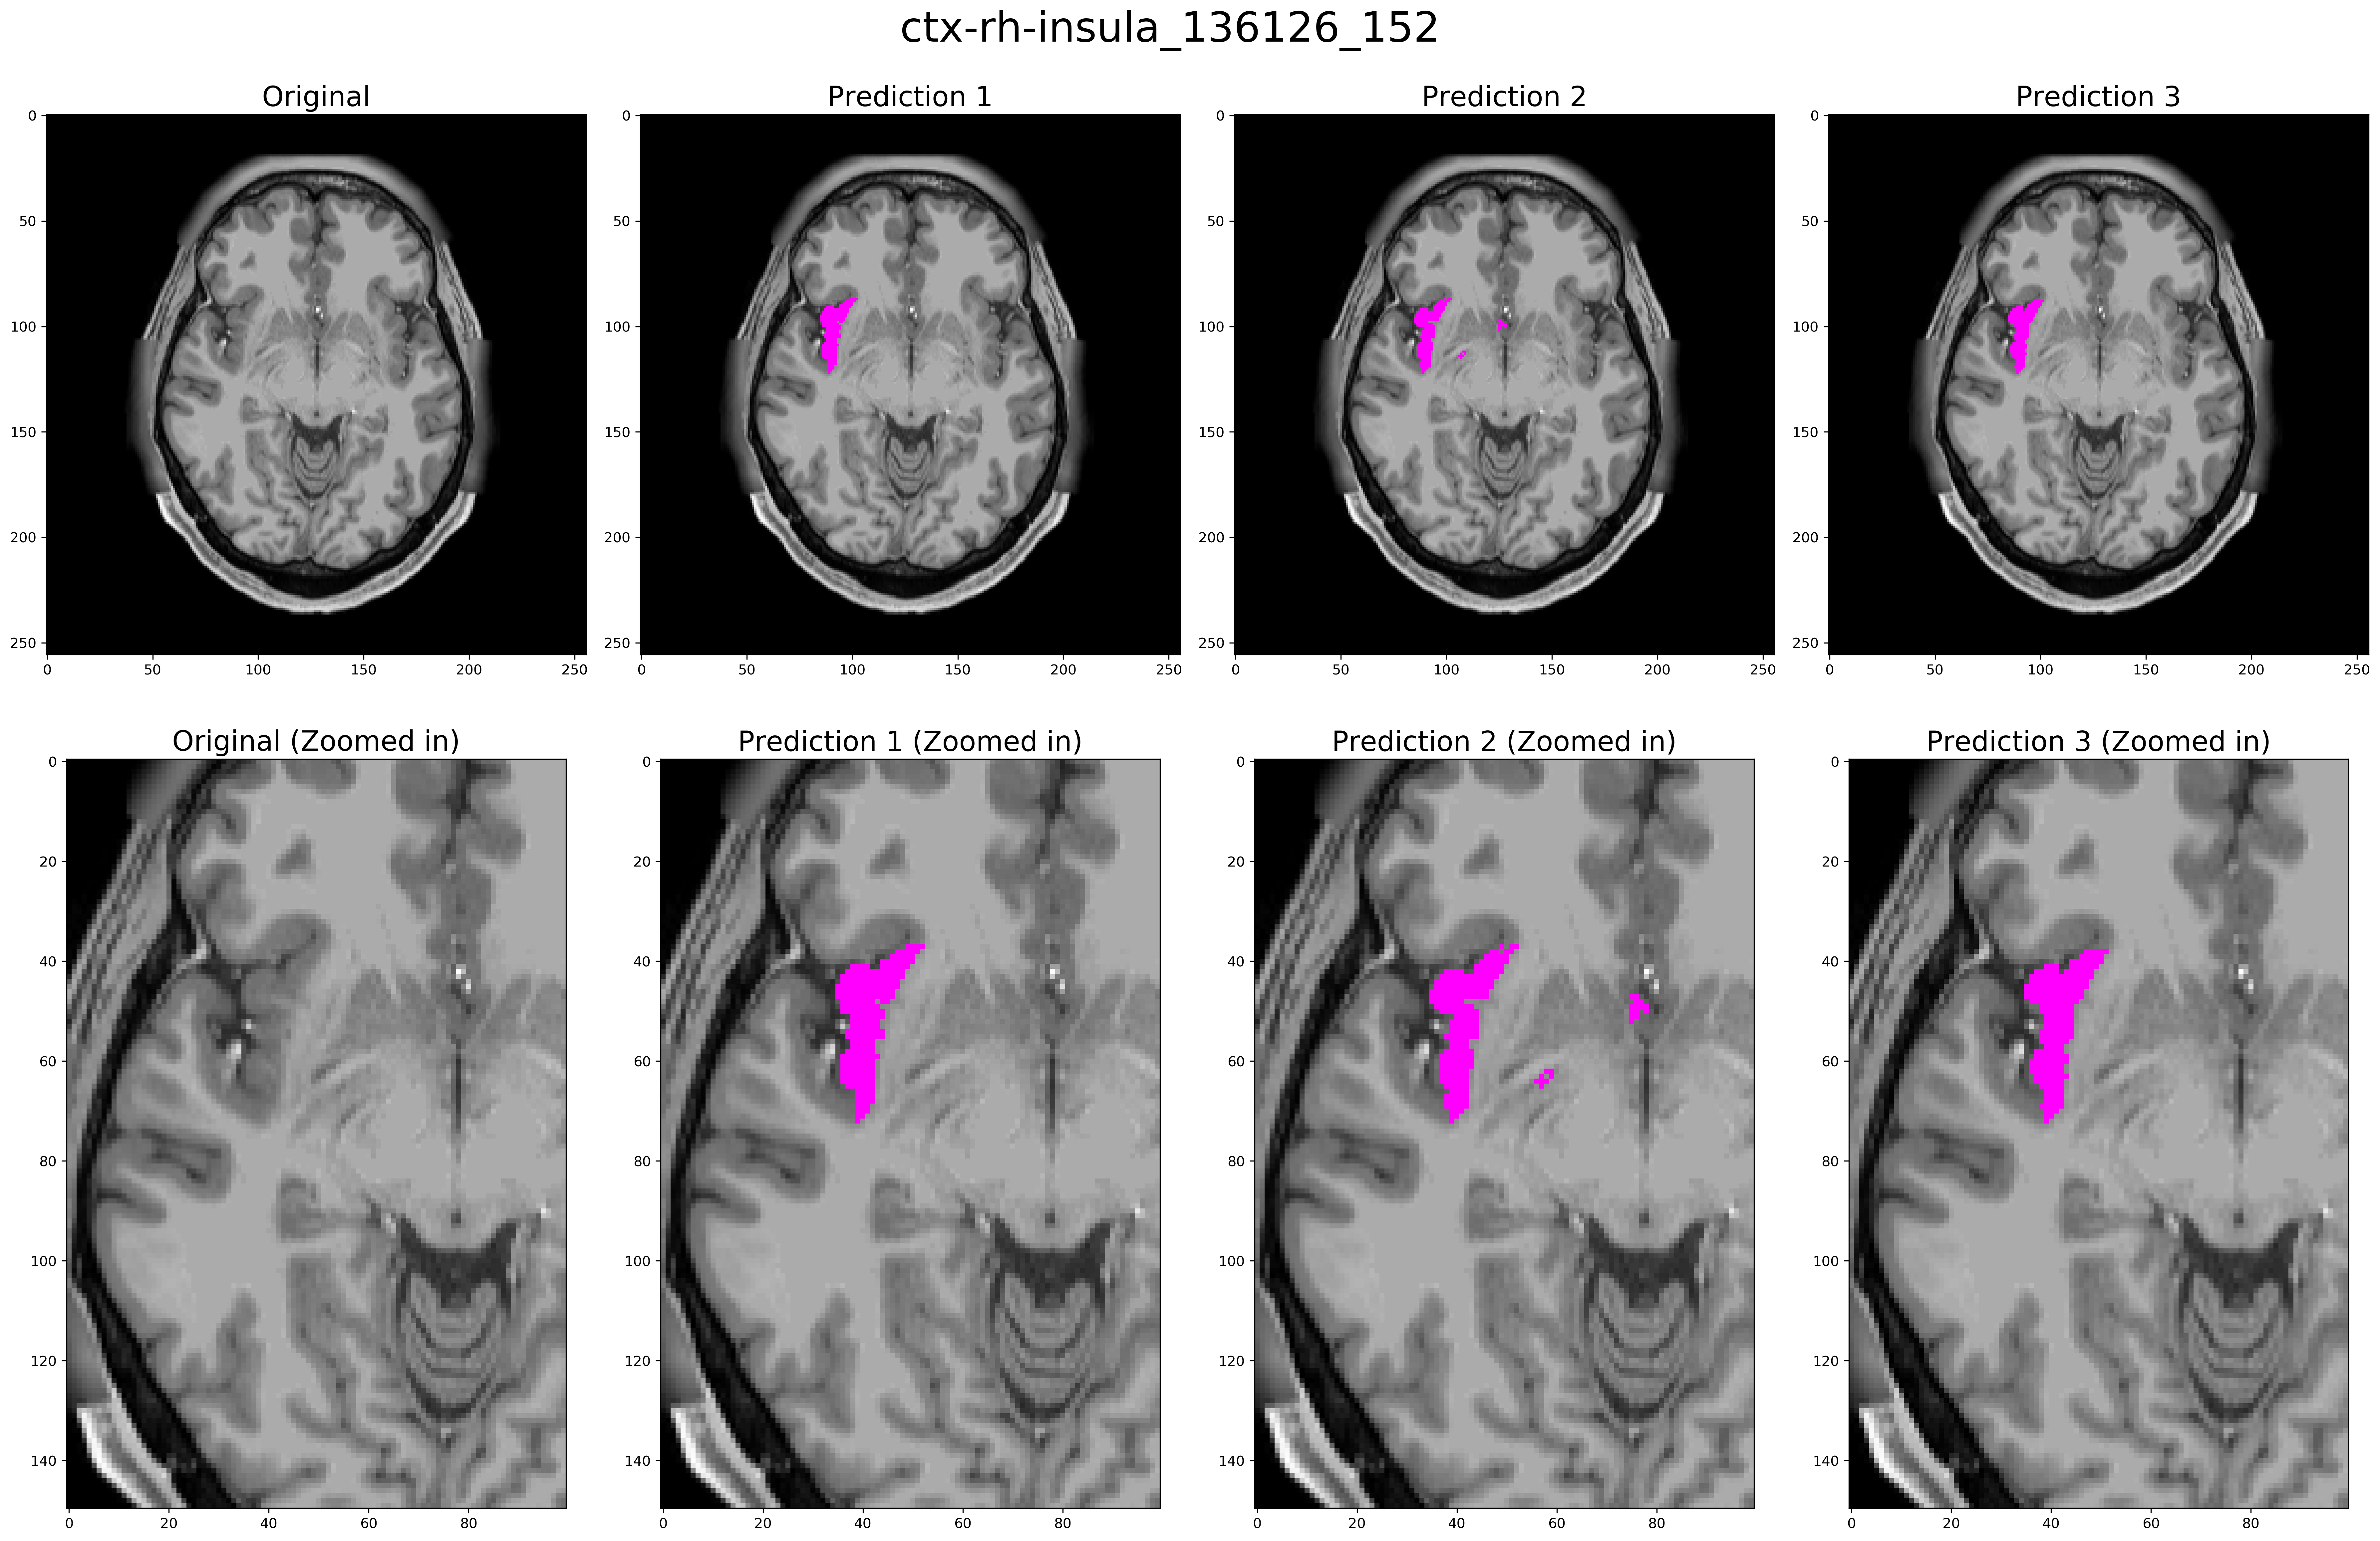

Three expert readers performed visual inspection and assessment of the segmentation results. There were two attending neuroradiologists with 3 and 5 years of experience and one second-year radiology resident. Each reader was asked to rate 40 different predictions for each ROI (20 in each brain hemisphere) such as shown in figure 2. Readers were blinded to the algorithm used to predict the segmentation and examples were presented in a randomized order. Each prediction presented consisted of a single slice containing a minimum of 40 pixels within the ROI, ensuring that enough of the structure being assessed was present on the given image. A sample slice rated by the readers is shown in figure 2.

Figure 2: A sample segmentation of Right Insula used in the expert reader evaluation. Here, predictions 1, 2 and 3 are from the Finetuned model, Freesurfer, and non-Finetuned model respectively; though in the reader study, numbering and order of presentation of the predictions are randomized and a total of 280 of examples are presented. Each reader is asked to rate each example for the quality of segmentation on a 5-point Likert-type scale.